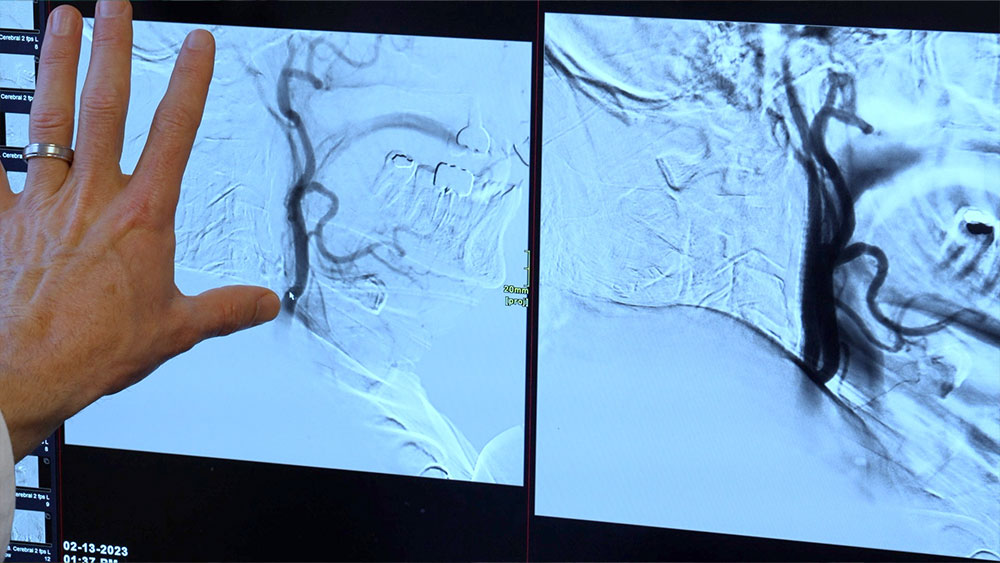

Within 20 minutes Dr. Dahlgren and his team were able to administer medication to break up the blood clot causing the stroke and put in stents to open up the blood vessels. When the blood flow was restored, Dr. Dahlgren said he could see that Kurt would be okay.